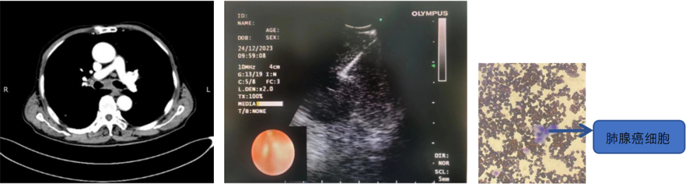

患者,男,70歲,近2個月來“活動后呼吸困難,近日又出現(xiàn)痰中帶鮮血”,收住院。胸部增強CT見“左肺下葉外周型占位,肺門、縱膈淋巴結(jié)腫大”。張強主任帶領(lǐng)團隊討論分析患者病情,高度懷疑為腫瘤性病變,且普通電子支氣管鏡獲取組織困難,病變緊貼主動脈,經(jīng)皮肺穿刺活檢風(fēng)險大。為明確診斷及分期,決定為患者實施支氣管內(nèi)超聲引導(dǎo)下針吸活檢術(shù)(EBUS-TBNA)+電子支氣管鏡下病灶活檢+現(xiàn)場快速評價(ROSE)。術(shù)中ROSE快速診斷查找到肺腺癌細胞,手術(shù)過程順利。最后病理檢查明確診斷為肺腺癌,為患者的下一步治療確定了方向。